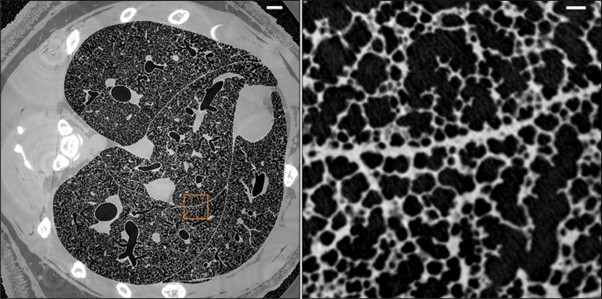

Stereology and µCT are the gold standard of volumetric and vascular reconstruction accuracy, and quantitative imaging modalities differ in the resolution of analysis at the morphometric scales (Table 1). Fig. 1 represents the workflow of the imaging and quantitative methods that were employed to analyze the morphometry of rat lungs. Fig. 2 [53] illustrates an example of high-resolution whole-lung reconstruction of a µCT of bronchial vascular architecture of intact rat lungs. The left panel is the horizontal slice of µCT that illustrates the global airway and parenchymal architecture of the rat lung, and the right one is the magnified view of the boxed area, which represents the detailed microstructure of the alveoli and acinar.

Fig. 2: Micrometer-resolution X-ray micro-CT of an intact post-mortem juvenile rat lung (reproduced from ref. [53], under CC BY 4.0 license).